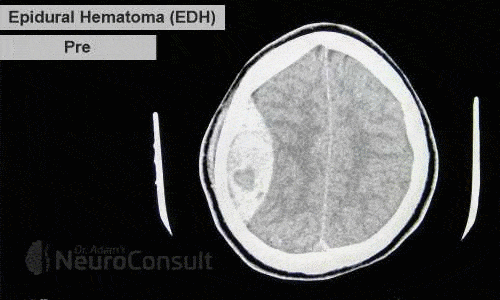

I am an consultant neurosurgeon. I have completed my Masters in General Surgery from SN Medical College, Agra and thereafter completed my formal Neurosurgical training from one of India's premier institute ie. SREE CHITRA TIRUNAL INSTITUTE OF SCIENCES AND TECHNOLOGY, Trivandrum (An institute of national importance). I have special interest in brain and spinal tumors.

I've been involved in numerous treatment of brain and spine-related ailments like spinal joint and disc disease, brain infarction(stroke/paralysis), hydrocephalus etc. to name the few. I am passionate about patient care and strives very hard for their recovery both physically and mentally.